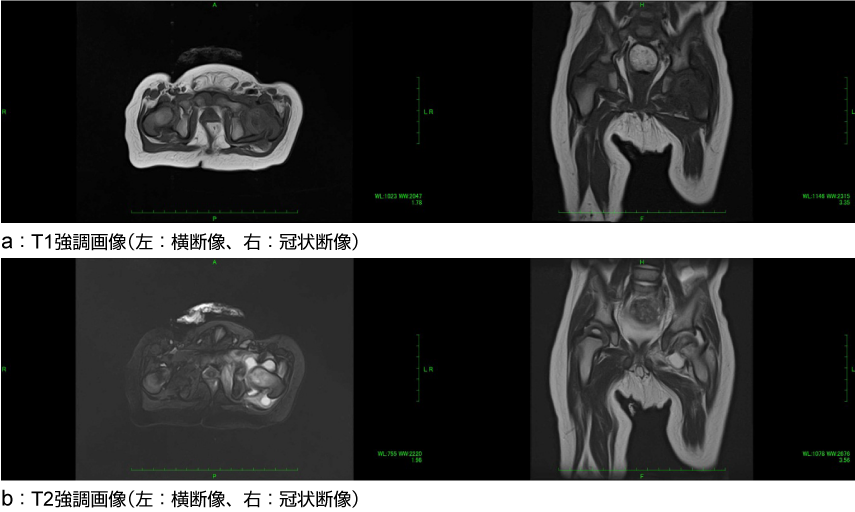

MRI(造影)

左化膿性股関節炎(11か月、男児)

他院で外科的処置がされず、抗菌薬の点滴静注が3週間行われた。血液検査で炎症反応は一次的に軽快したが、股関節炎は鎮静化せず、当院を紹介されて受診した。

MRIでは、左股関節液の貯留が著明であり、周囲軟部組織と骨髄の炎症所見を認める。

a:T1強調画像(左:横断像、右:冠状断像)

b:T2強調画像(左:横断像、右:冠状断像)